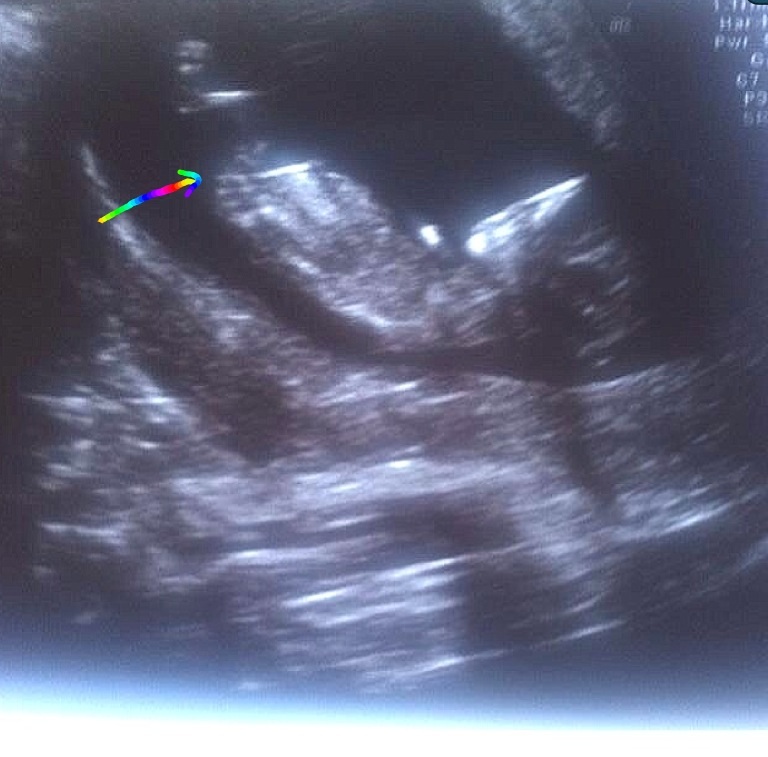

Hi ladies. Is this the nub where I have the arrow In the pic? If so, what do you think the gender is please? Xx